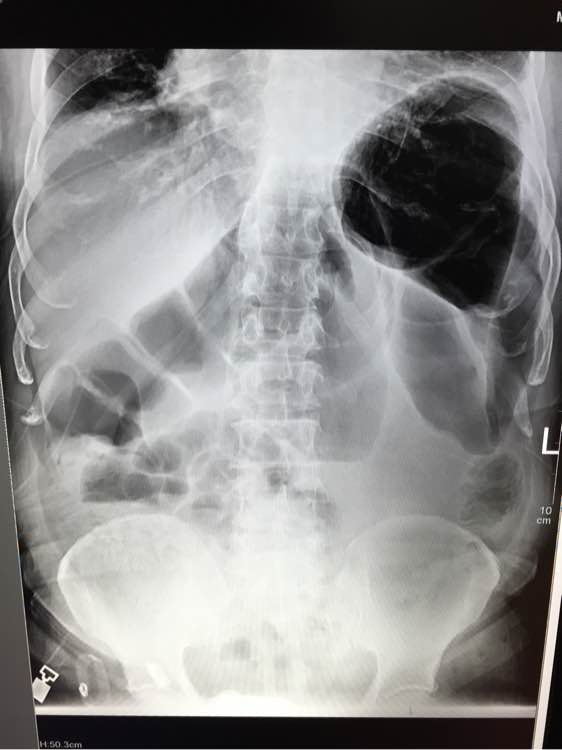

腹痛1天 从x片可以看出什么问题啊